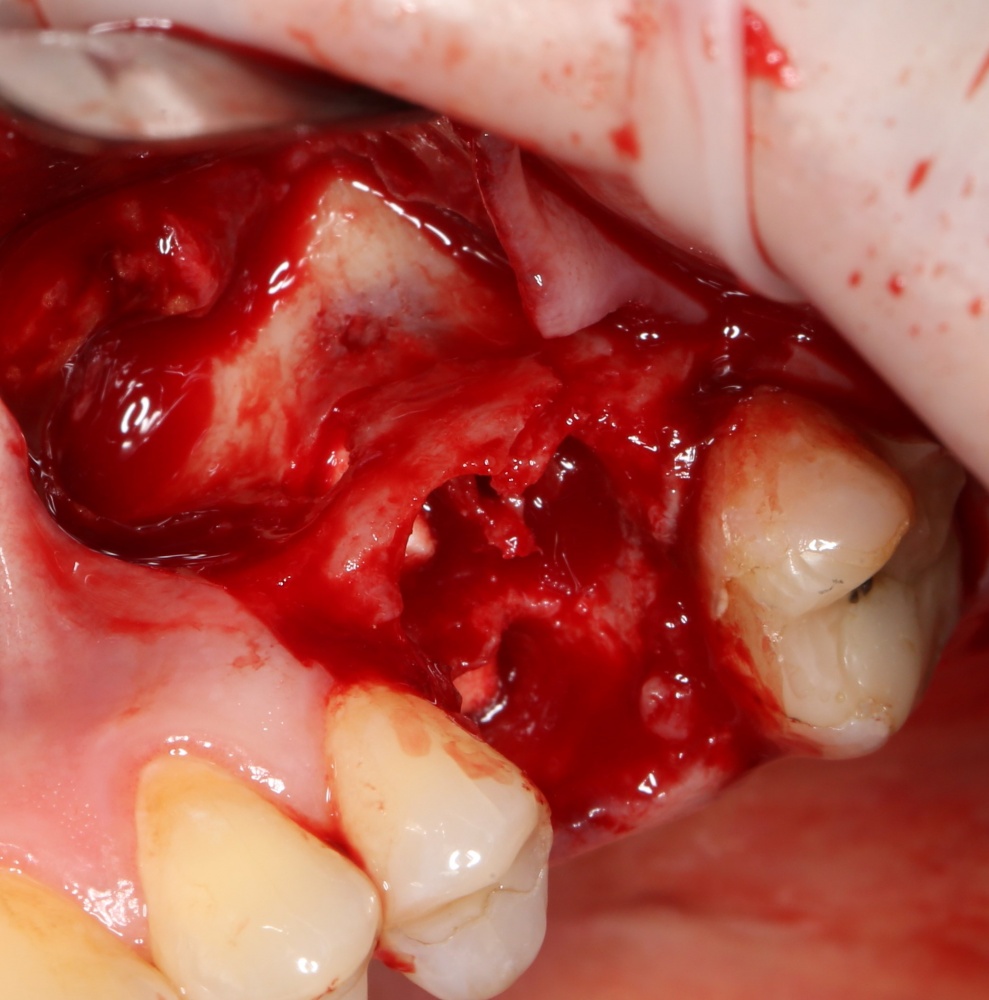

Вот ситуация:

По ряду причин, мы вынуждены удалить верхнюю шестерку и заменит ее на имплантат.

Все начинается с удаления зуба:

Обратите внимание на состояние вестибулярной стенки лунки. В проекции верхушек корней вы можете увидеть костный дефект, вызванный длительным воспалительным процессом (собственно, почему этот зуб пришлось удалять). В этом случае, вестибулярная стенка лунки неизбежно лизируется после удаления зуба, а это приведет не только к проблемам в эстетике, но и осложнит последующий уход за протетической конструкцией. Поэтому в данном случае мы должны продумать, в том числе, аугментацию лунки. И порядок действий здесь несколько иной, нежели в предыдущем случае.